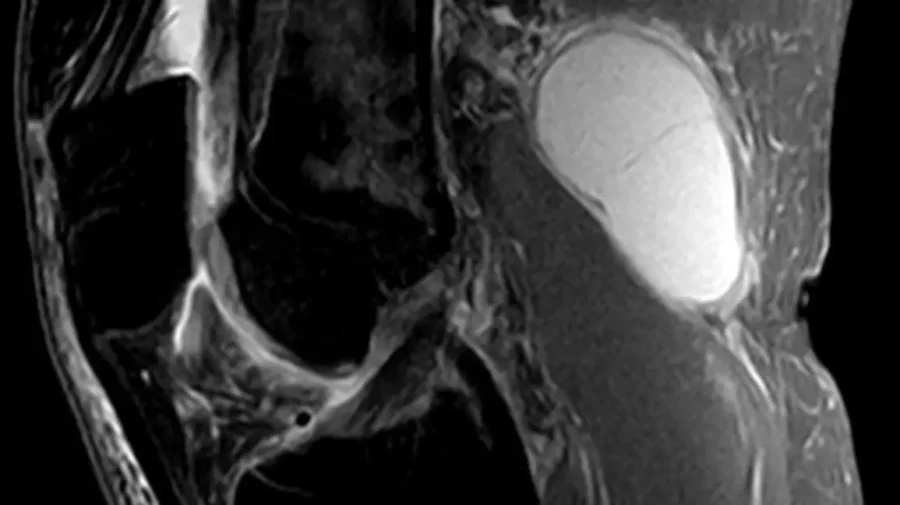

Киста Бейкера — это опухший, заполненный жидкостью мешок в задней части колена.

Причины кисты Бейкера включают состояния или явления, которые влияют на суставы, такие как артрит, воспаление от повторяющихся нагрузок или повреждение хряща. Киста Бейкера может вызывать воспаление и боль, а также снижение диапазона движений в колене.

Физиотерапия, дренирование жидкости и лекарства могут быть использованы для лечения кисты Бейкера.